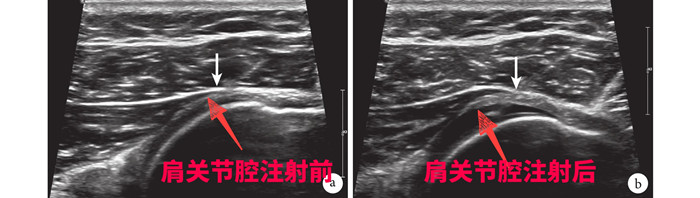

針對劉大爺?shù)那闆r,徐慧勝制定了個(gè)性化治療方案“體外沖擊波結(jié)合超聲引導(dǎo)下肩關(guān)節(jié)注射治療”,先采用沖擊波松解肩關(guān)節(jié)周圍黏連的組織,然后在超聲引導(dǎo)下將消炎鎮(zhèn)痛液準(zhǔn)確注射到肩關(guān)節(jié)腔、滑囊及神經(jīng)周圍,起到雙管齊下的作用。15分鐘后,劉大爺感覺疼痛減輕了大半,活動明顯改善。經(jīng)過3次治療,劉大爺?shù)募缰苎滓鸦局斡?